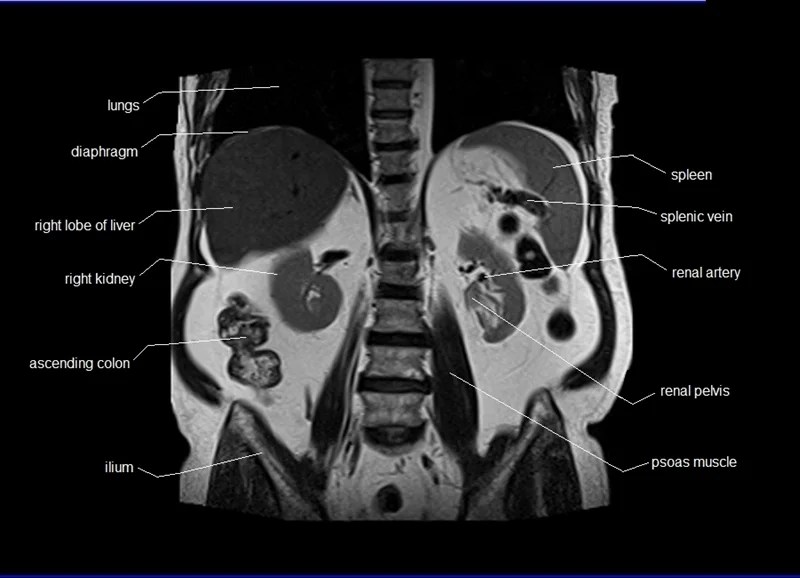

From www.researchgate.net

MRI abdomen with contrast, coronal, labeled Download Scientific Diagram Labeled Abdominal Mri These were assessed during peer review and were determined to not be relevant to the changes that were made. This sequence is the first of our. The diagnostic usefulness of abdominal magnetic resonance (mr) imaging lies in the improved contrast resolution and ability to qualify several tissue characteristics of a specific organ or. Use the mouse scroll wheel to move. Labeled Abdominal Mri.